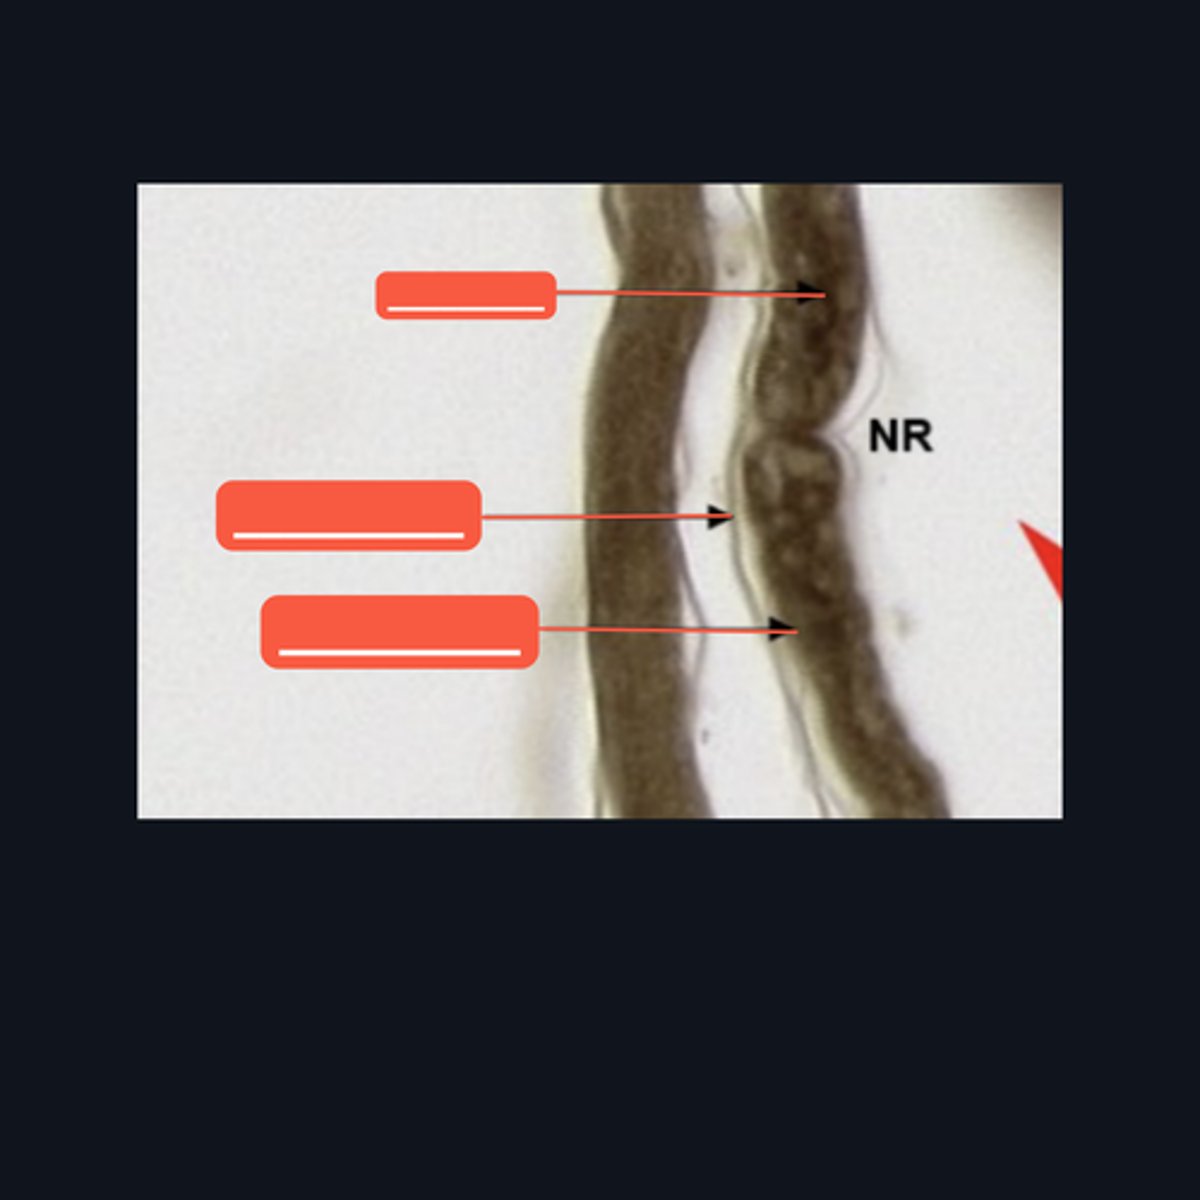

Peripheral Nerve

Identify where this structure is found

(top 3) from left to right

Perineurium

Axon

Myelin sheath

(bottom 2) from left to right

Endoneurium

Schwann cell

Identify the pointed structures.

Peripheral Nerve

Identify the structure on the image.

(top to bottom)

Axon

Endoneurium

Myelin sheath

Identify the pointed structures.